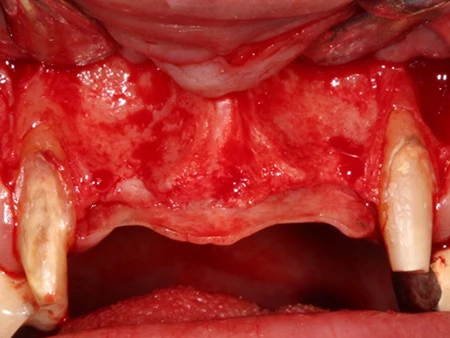

歯ぐきを開き、移植する部位の骨を確認します。